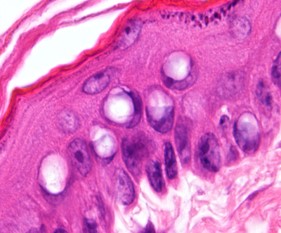

皮脂腺腫

皮脂腺上皮の良性腫瘍で、皮脂の分泌物が貯留し、皮膚を透かして内容物が蜂の巣状に見えるが特徴です。全身のあらゆる箇所に発生します。